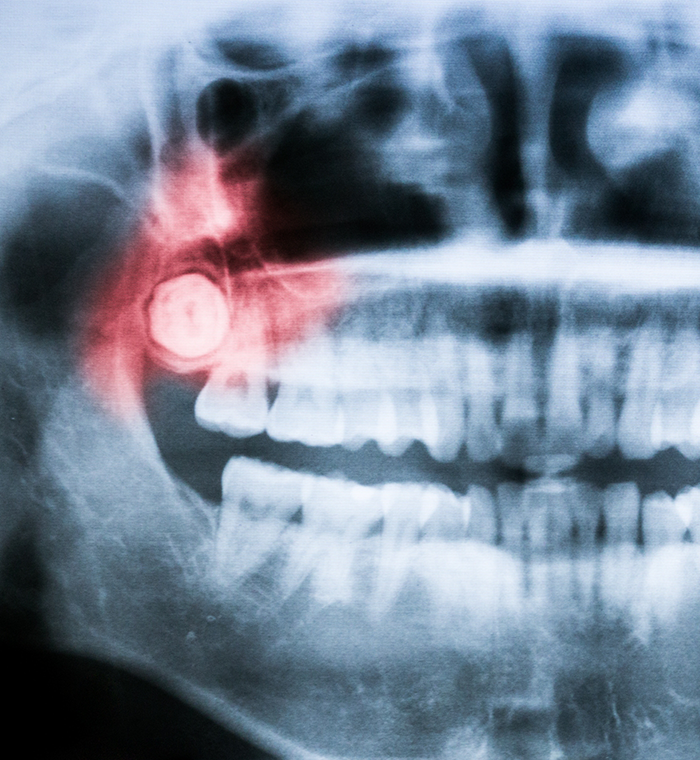

When an adolescent or young adult is between the ages of 16 and 25, the third set of molars – wisdom teeth – are likely to erupt. If you have a teenager or adult child within this age range, they may complain of discomfort in the back of their mouth. These teeth, once essential for early civilizations to maintain their diet, no longer serve a purpose but instead cause pain, misalignment, and often, poor oral health. Instead of allowing these issues to continue, we can easily remove these molars with wisdom tooth extractions in Springfield or Neptune. Dr. Alkamary understands you probably have many questions about the procedure, so do not hesitate call our office to schedule an appointment.

The Wisdom Tooth Extraction Process

Glamorous Smile Dental Spa is equipped with the most advanced, state-of-the-art technologies so that Dr. Alkamary can perform wisdom tooth extraction with ease. Whether it is you or your teenager who requires this procedure, she will start by making sure you are comfortable, using local anesthesia, patient-friendly amenities, and sedation if requested.

Once she determines the state of each molar, she will either remove it with a simpler process that involves elevating the tooth and using pliers to move it back and forth until it detaches, or she will opt for a surgical approach.

If the tooth cannot be seen above the gumline, it will require opening the gums and exposing the tooth and bone. To avoid causing additional damage to the bone, she will likely divide the tooth into sections for easier, less stressful removal.